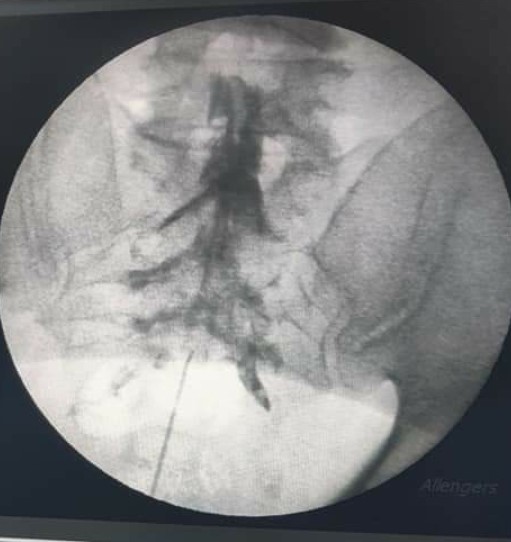

Epidural space is a potential space present in the Spinal canal around the spinal cord. Epidural MIPSI is a procedure in which an anti-inflammatory medication is injected in this Epidural space with the help of a needle under X ray guidance at the level where the patient has the actual problem. Caudal Epidural MIPSI is a technique wherein the Epidural space is accessed through the Sacral hiatus, which is an opening on the posterior aspect of the sacral bone.

• Caudal Epidural injection: In this needle is inserted through sacral hiatus till the S2 level and the solution is injected before confirmation of the location with a radiocontrast dye.